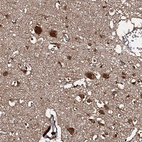

Immunohistochemical staining of human cerebral cortex shows strong cytoplasmic positivity in neurons.